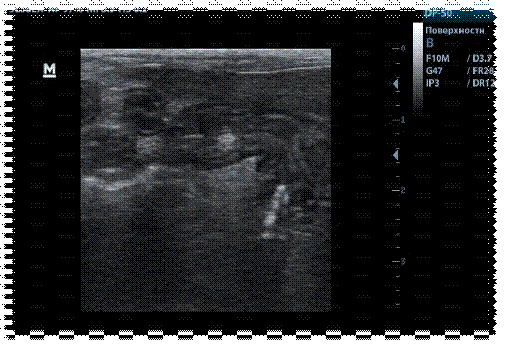

10. Другие исследования Ультразвуковое исследование брюшной полости.  Заключение: Диффузное утолщение складок слизистой оболочки желудка; эхогенность стенки повышена, структура однородная. Диффузное утолщение стенки слизистой оболочки тощей кишки. Лабораторные исследования Общий гематологический анализ Лейкоциты - 24, 7х 10⁹/л (10-20*10⁹/л) ↑ Эритроциты - 6,4 х 10⁹/л (5,0-7,5*10¹²/л) Гемоглобин - 119 г/л (110-140 г/л)  Гематокрит - 33% (26-48%) Цветовой показатель - 0,84 (0,65-1,0) Сегментоядерные нейтрофилы - 43% (40-45%) Палочкоядерные нейтрофилы - 12% (3-9%) ↑ Лимфоциты - 48% (36-51%) Эозинофилы - 4% (2-8%)  Моноциты - 3% (1-5%) Тромбоциты - 402 х 10⁹/л (100-500 *10⁹/л) Заключение: Лейкоцитоз,  нейтрофилия со сдвигом ядра влево.

Заключение о проведенном УЗИ указывает на диффузное утолщение стенок желудка и тощей кишки без структурных изменений. Усиление перистальтики тонкого кишечника.

Рис.2 Сонография тонкого отдела кишечника у кошки. Диффузное утолщение слизистой оболочки тощей кишки